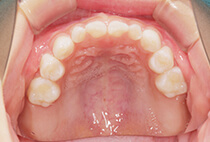

20代女性の患者さま。

八重歯の見た目が気になってご来院されましたが、実は顎の痛みや開口障害など、顎関節症の症状もありました。

そのため、かみ合わせと顎関節症の治療を同時に行ったにもかかわらず、2年間で治療が終了。

かみ合わせが整い咬筋の過緊張も改善しました。咬筋の肥大も治ってフェイスラインがすっきりしました。

最終的には美しい歯並びと、安定した痛みのないかみ合わせが実現しました。

八重歯が気になる

叢生、顎関節症、開口障害

しっかり前歯を下げるために、インプラントアンカーを使用してコントロールしました。

かみ合わせが整うと咬筋の過緊張が改善。

過緊張による筋肉肥大も改善しフェイスラインもすっきりしました。

治療前

治療後